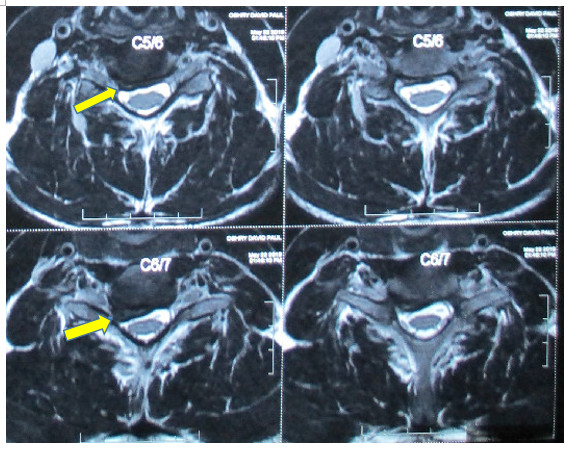

39歲的David是一位職業模特兒,今年2月因做舉重運動時扭傷了頸部,初時以為是肌肉發炎,但兩星期後仍然覺得頸部及手部痠軟無力、痺痛。接受了X光檢查,在X光片上沒有發現任何骨骼病變或椎孔收窄的情況,看起來應不是椎間盤突出的症狀,醫生便開了消炎止痛及鬆弛肌肉的藥物。初時服了藥物後是紓緩了一點,但相隔了兩個月後發現上手臂及右肩背肌肉有萎縮的跡象,而且在舉重時上手臂不能夠發力,感覺手軟、身體開始無力!筆者觀察他的肌肉萎縮情況並了解病歷後,認為應該是椎間盤突出的原因,由於X光片上只能看見頸椎第六、七節椎間輕微收窄了一些,而在照椎孔那張X光片上又看不見頸椎第六、七節有收窄的現象,相信單靠X光並不能夠為他確診出任何原因,後來筆者在診所內幫他做了磁力共振掃描,發現他頸椎第六、七節有一個頗大的椎間盤突出壓向右邊神經根,這處便是影響他右邊肩背、手部肌肉萎縮及右手無力的原因,而頸椎第五、六節間也有椎間盤突出,這便是造成他右手麻痺的因素。

透過磁力共振掃描,可見到案例一患者頸椎第六、七節有一個頗大的椎間盤突出壓向右邊神經根,而頸椎第五、六節間也有椎間盤突出